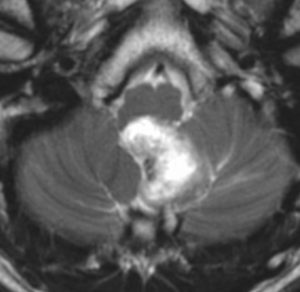

簡単な手術となる例

左右の写真は異なった患者さんのものです。両者ともに,大きな嚢胞(水たまり)を伴う小脳内部の小さな血管芽腫です。右の方に小さく白い塊(黄色の矢印)が見えるのですが,それだけが腫瘍で,濃い灰色に見える部分はのう胞といって液体がたまっているだけです。

これはとても(といっては何ですが比較的に)簡単な手術例です。小脳失調によるふらつきや水頭症よる頭痛と嘔吐などを出しますが,手術後に症状は改善します。

一般に小脳半球という場所にできたものは大きくても手術の成功率はとても高いです。小さいものでは場所と症状によってはガンマナイフなどの放射線治療も有効なことがあります。しかし,手術で摘出できるものは摘出した方が確実に治ります。